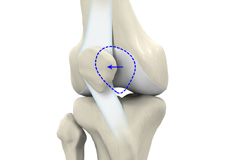

Patellar Instability

Any damage to the supporting ligaments may cause the patella to slip out of the groove either partially (subluxation) or completely (dislocation). This misalignment can damage the underlying soft structures such as muscles and ligaments that hold the kneecap in place.

Patellofemoral Instability

Patellofemoral instability means that the patella (kneecap) moves out of its normal pattern of alignment. This malalignment can damage the underlying soft structures such as muscles and ligaments that hold the knee in place.